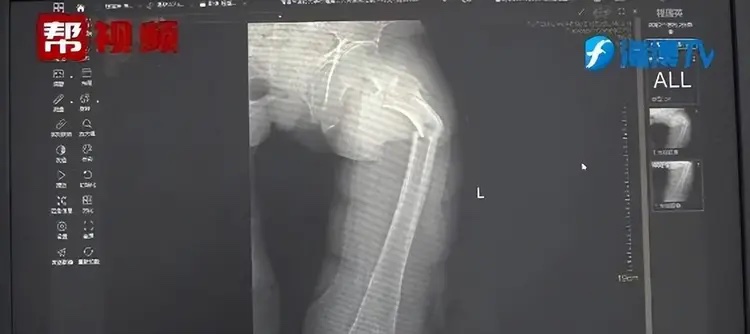

02/06/2024 15:41Người đàn ông 35 tuổi bị gãy xương cứng nhất cơ thể trong một cơn ho dữ dội

Theo trang Oddity Central (Anh), các bác sĩ tại Bệnh viện Nhân dân số 2 ở tỉnh Phúc Kiến, Trung Quốc, gần đây đã báo cáo trường hợp gây sốc của bệnh nhân họ Ye, 35 tuổi, bị gãy xương đùi trong một cơn ho.

Bác sĩ Dong Zhong, Giám đốc Khoa Chỉnh hình tại bệnh viện, cho biết bệnh nhân đã gặp sự cố này trong cơn ho. Điều này là bất thường vì nam giới trong độ tuổi của anh Ye thường chỉ bị gãy xương đùi do chấn thương nghiêm trọng, chẳng hạn tai nạn xe hoặc ngã từ độ cao đáng kể.

Ye nói với các bác sĩ rằng anh cảm thấy đau nhói ngay sau cơn ho dữ dội, nhưng anh nghĩ rằng mình chỉ bị chuột rút. Chỉ sau khi cảm thấy khó đi lại, anh mới quyết định đến bệnh viện để kiểm tra.

Phim chụp X-quang cho thấy anh Ye bị gãy xương đùi. Các bác sĩ khi đó cũng chưa thể chứng minh rằng cơn ho của anh có ảnh hưởng gì đến chấn thương vật lý này.

Bác sĩ Zhong và nhóm của ông quyết định điều tra thêm. Họ đã kiểm tra sức khỏe tổng quát, thói quen ăn uống và lối sống của bệnh nhân. Họ cũng tiến hành xét nghiệm mật độ xương và thu được kết quả đáng lo ngại. Mật độ xương của anh Ye tương tự như mật độ xương của một người đàn ông 80 tuổi, điều này rất bất thường, ngay cả đối với những người đàn ông hiện đại ít vận động.

Sau khi các xét nghiệm xác nhận rằng Ye không mắc bất kỳ bệnh gì về xương, các bác sĩ kết luận rằng anh có xương cực kỳ giòn do thói quen uống coca, chế độ ăn uống kém và thiếu vận động.

Người đàn ông 35 tuổi này thừa nhận với các bác sĩ rằng anh thường uống đồ uống có ga thay nước lọc. Các bác sĩ giải thích điều này dường như đã ngăn cơ thể của Ye hấp thụ canxi đúng cách, do đó ảnh hưởng đến mật độ xương của anh.

Theo bác sĩ Zhong, đồ uống thành phần cola có chứa axit photphoric, kết hợp với canxi trong thức ăn thông thường có thể tạo thành canxi phosphat sau khi đưa vào cơ thể. Cơ thể con người rất khó dung nạp chất này. Vì vậy, tiêu thụ những loại đồ uống có ga thường xuyên trong thời gian dài có thể gây ra hệ quả tàn khốc đối với mật độ xương.